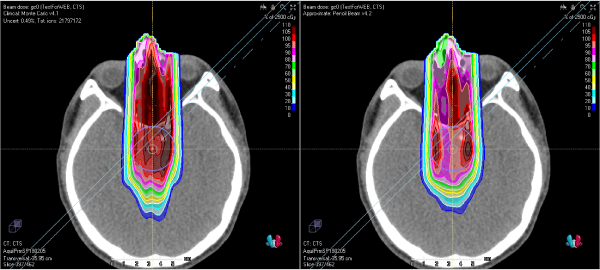

陽子線治療を含めた放射線治療では、どこにどの程度の線量が照射されるか事前に計算します。その計算はとても複雑で、実用的な時間でより正確に計算できるよう様々な手法(「線量計算アルゴリズム」といいます)が今まで多数開発され進歩してきました。陽子線が器具や人体中の骨や空気などの物質を通過すると、エネルギーを失うだけでなく、進行方向に対して側方に散乱されてその軌道が曲げられます。従来の線量計算アルゴリズムでは、側方に散乱された影響の計算に関して精度に限界がありました。これをより正確に計算することを可能にする線量計算アルゴリズムとしてモンテカルロ法といったものがあります。当センターでは2019年より、このモンテカルロ法を使った治療を開始しました。

モンテカルロ法によって計算された陽子線の線量分布(左)と

従来の線量計算アルゴリズムによる線量分布(右)